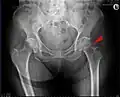

-

Mediale Schenkelhalsfraktur ohne Dislokation -

Laterale Schenkelhalsfraktur mit Adduktions-Dislokation -

Im Vergleich dazu ein gesundes Hüftgelenk